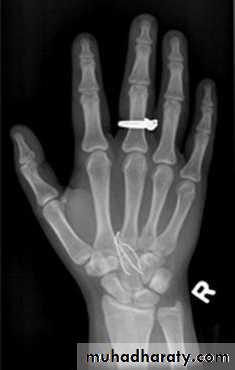

-X-rays were discovered by Konrad Rontgen in 1895 while he was experimenting with cathode tubes. found out that x-ray was attenuated in a different way by various kinds of materials and that it could, like light, be captured on a photographic plate .-This opened up the way for its use in medicine. The first “Rontgen picture” of a hand was made soon after the discovery of X-rays.

According to x- ray attenuation in the tissues ( x – ray penetration) ,the radiographic appearace can be graded into :

Moderate radio-opague as bones and calcifications

Dense radio-opague as metals and contrasts